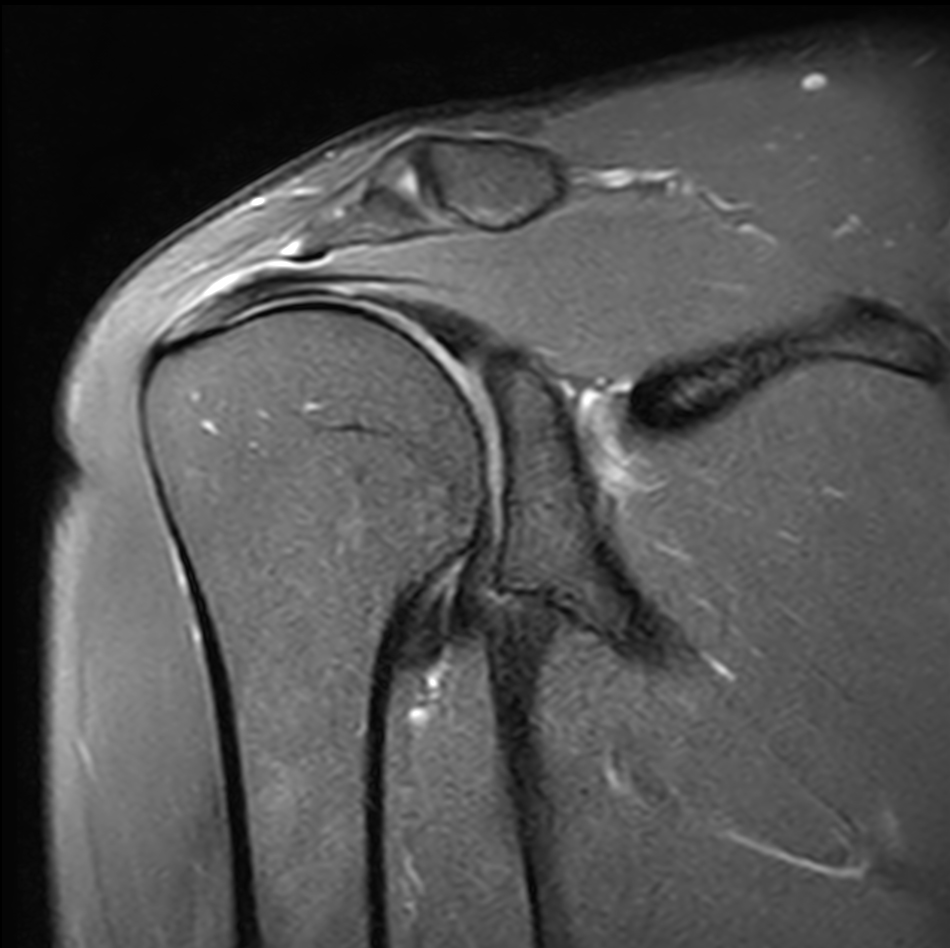

Sagittal T2w TSE